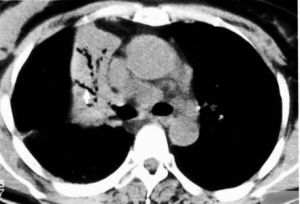

肺實變體徵

肺實變體徵是指任何原因致肺泡腔內積聚漿液、纖維蛋白和細胞成分等,使肺泡含氣量減少、肺質地緻密化的一種臨床體徵。